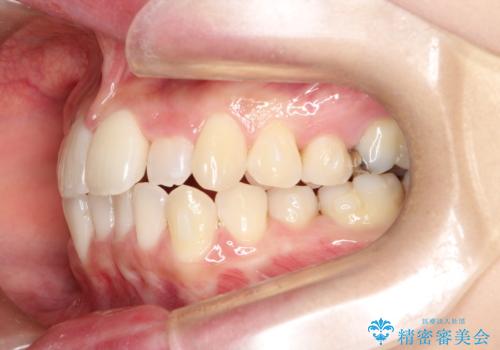

- 前歯の正中離開の改善を希望され来院された患者様です。

初診時の歯並びの状態としては、上下ともに前歯部の中等度のがたつきがあり、特に左上の前歯が1本内側に入り込んでしまっている状態でした。

また、2mm程度の正中離開がありました。

抜歯なし/インビザラインによるマウスピース矯正にて治療を行いました。

内側に入り込んでしまっている歯を出してくることに非常に時間がかかりましたが、一度歯を歯茎の方へ押し込みそして前へ出してくる2段階の治療を行いました。

見た目、噛み合わせ及び、治療期間や施術内容に大変ご満足いただきました。